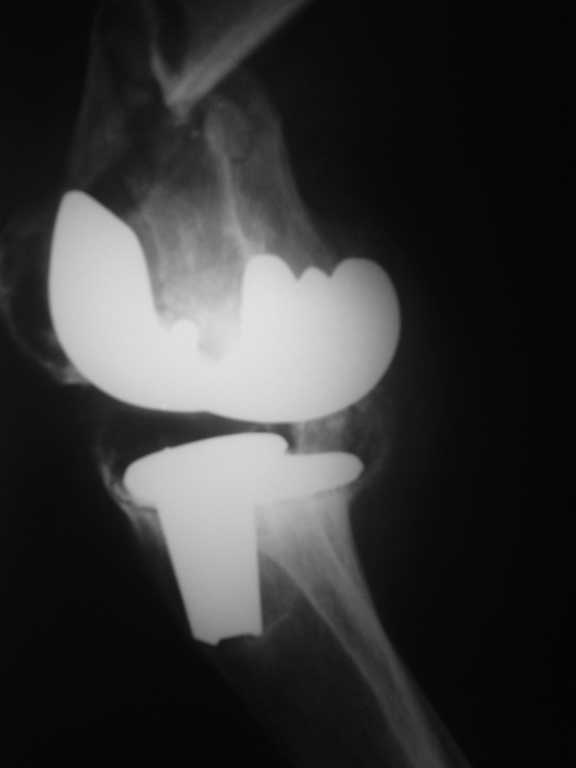

Пациентка 54 г. Два года назад выполнено протезироввние коленного сустава в одном из федеральных учереждений.

Обратилась на консультацию в связи с выраженым болевым синдромом. В тот момент находилась на лечении в терапевтичесом отделении по поводу язвенной болезни желудка. При осмотре клинико-Рлогическая картина нестабильности компонентов протеза. рекомендовано оформление инвалидности и реэндопротезирование по квотам. Через неделю пациетна упала. в результате падения переипротезный перелом на фоне нестабильного протеза. Переведена в травм.отд. наложено скелетное вытяжение. Какие варианты лечения возможны? Финансово несостоятельна.

Его (при грамотном применении) никто не отменял и на ревизию здесь ничто не повлияет. Тем более судя по снимкам имеется нестабильность тибиального компонента а про бедренный компонент не убедительно. Пока больна дождется квоты (учитывая нашу действительность) глядишь и перелом бедра срастется не вытяжении.